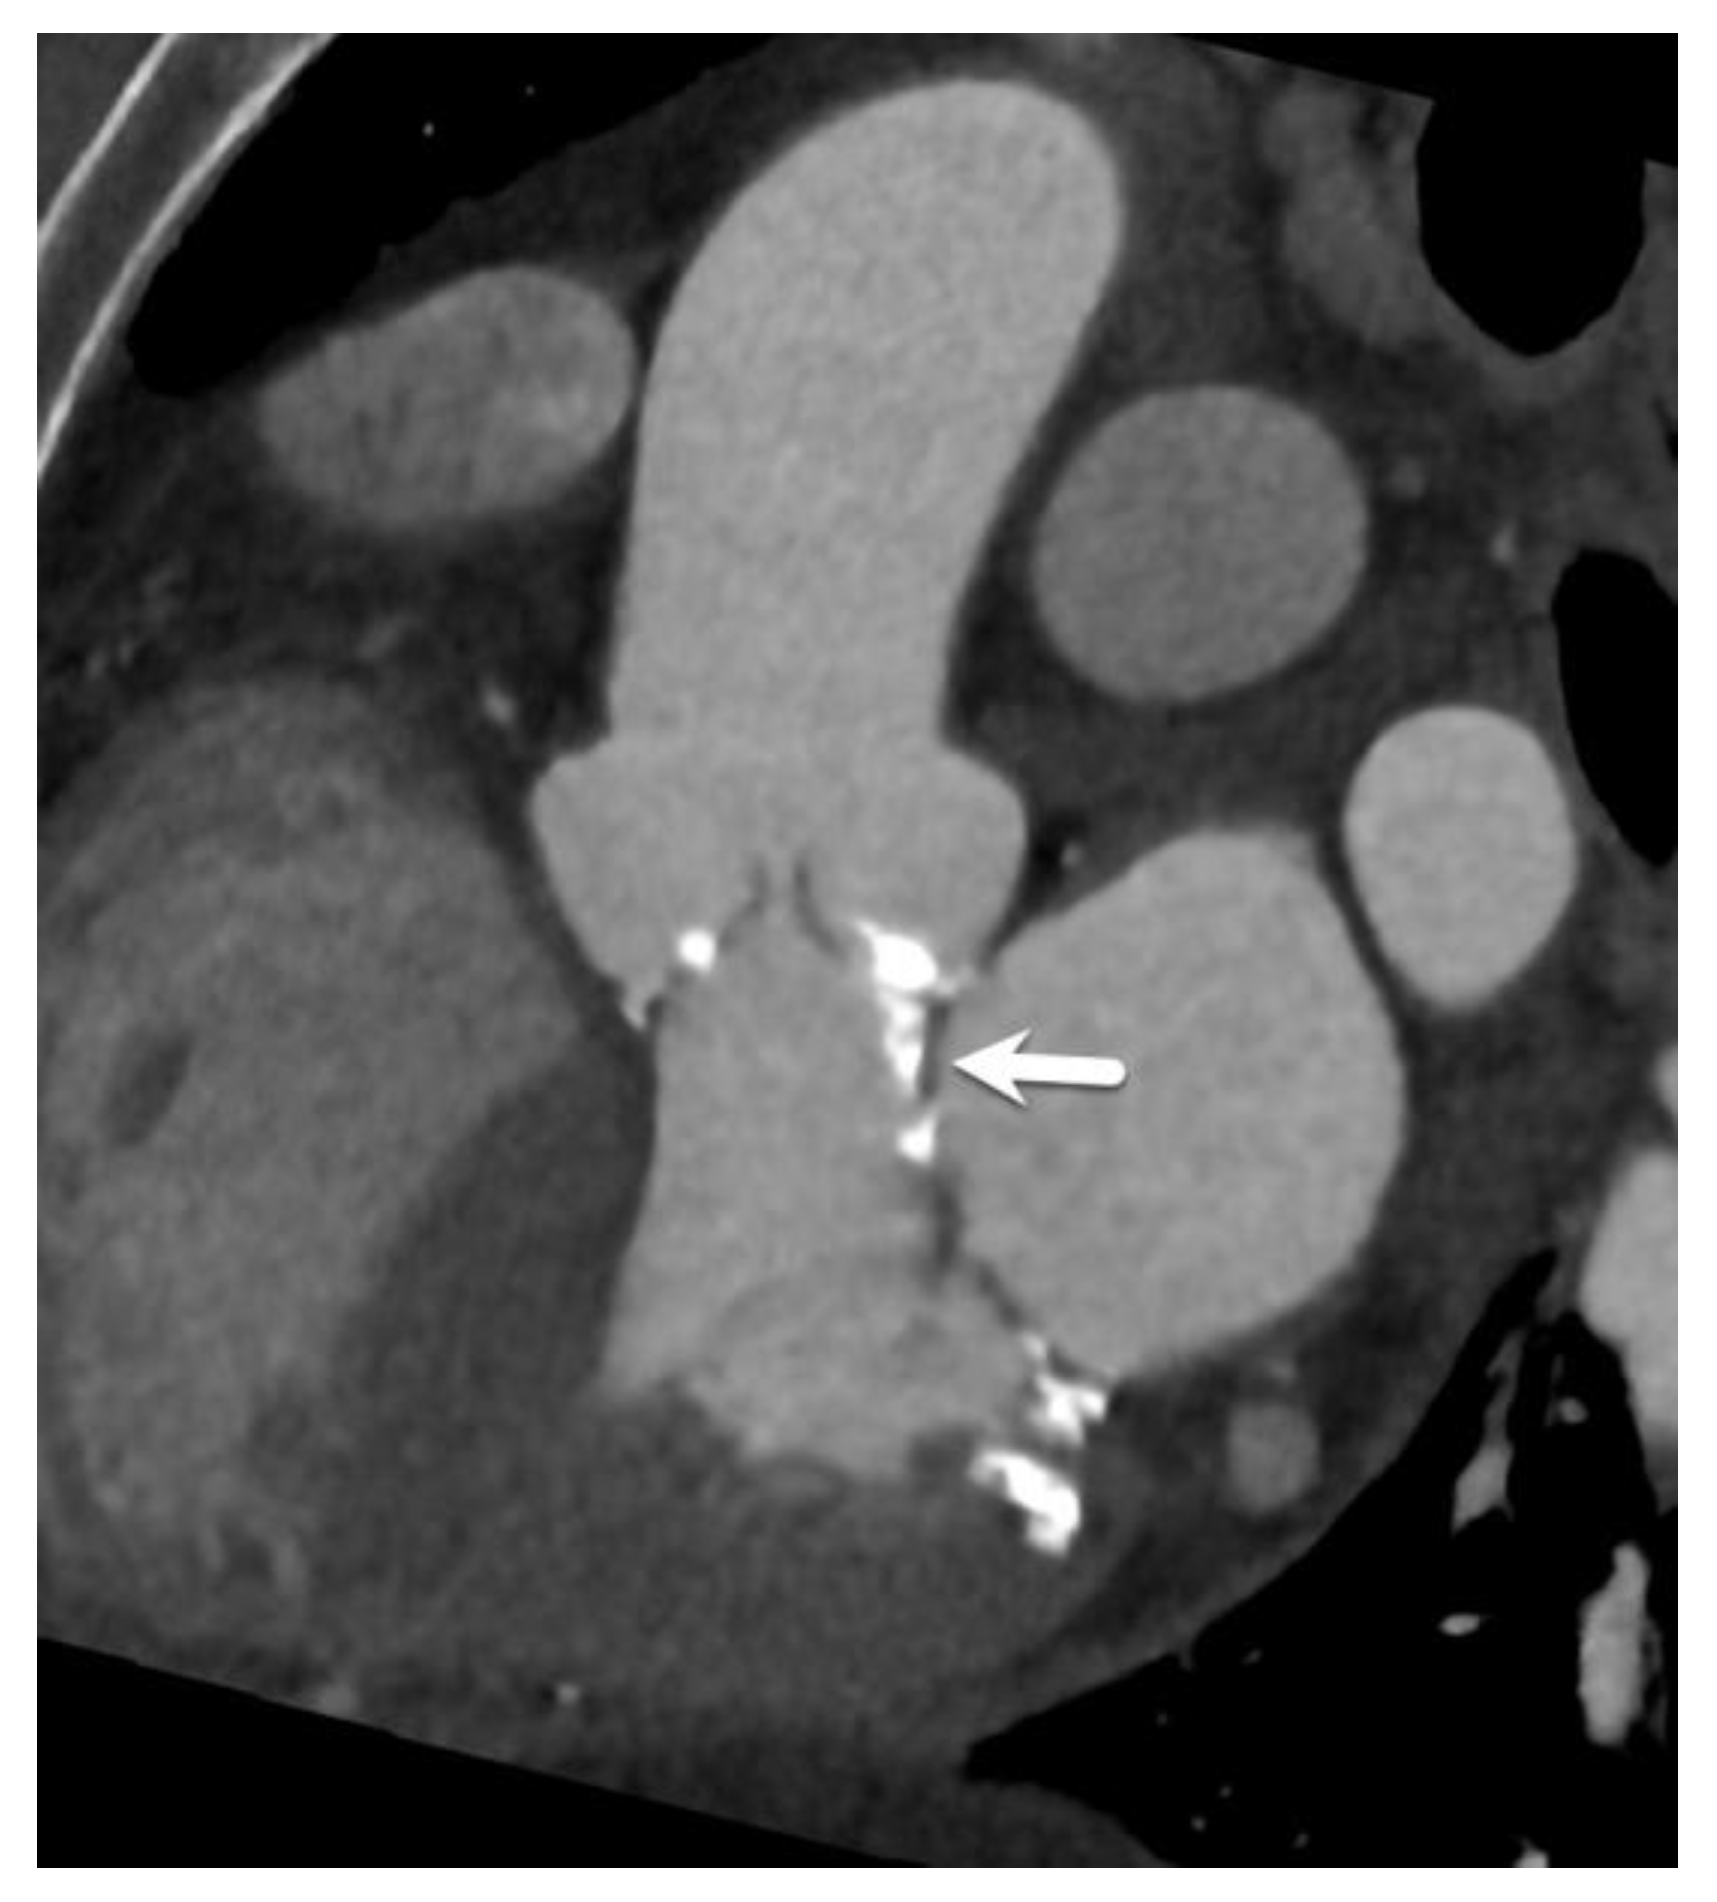

5. Transcatheter Tricuspid Valve Replacement